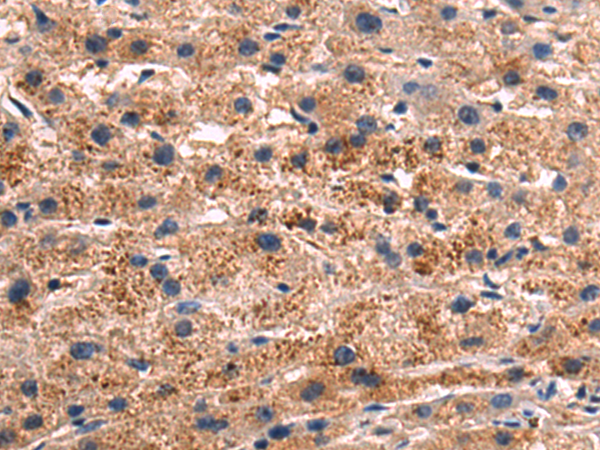

分类: 科研抗体货号: P10621别名: POR1应用: IHC反应种属: Human, Mouse, Rat